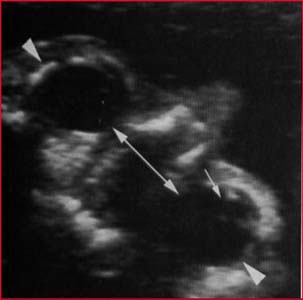

Hypertélorisme